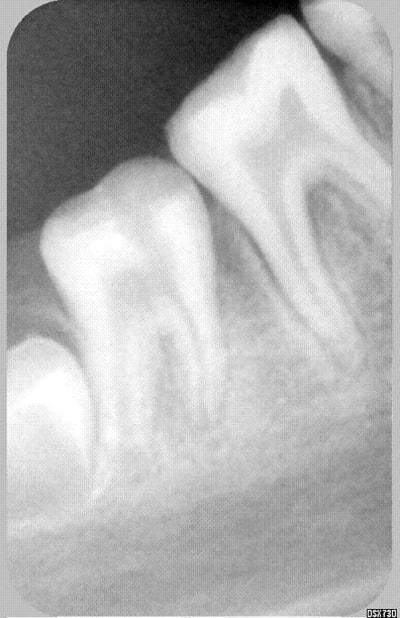

ci joint la 37...c'est drole hein?!...

37;perte de densité vestibulaire.